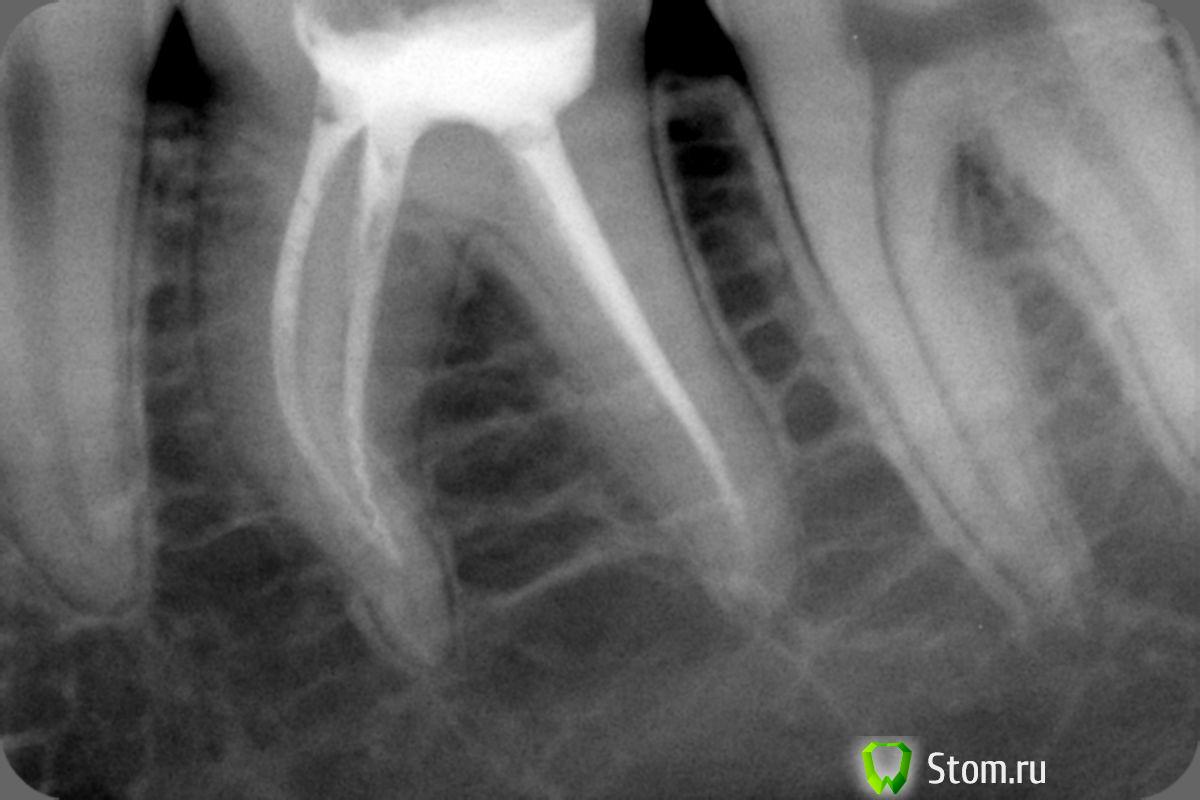

uWn Опубликовано 23 апреля, 2012 Автор Поделиться Опубликовано 23 апреля, 2012 скорее всего шишка связана с восполительным процессом в обл зуба мудрости, если так, то удалять надо. Но снимки все таки постарайтесь скинутьВот снимок участка с шишкой в момент, когда она увеличилась. С пломбой - 6 зуб Ссылка на комментарий

uWn Опубликовано 20 апреля, 2012 Автор Поделиться Опубликовано 20 апреля, 2012 (изменено) в электронном виде снимок только в понедельник смогут отправить на почту, а с распечатки ужасного качества скан получился... шишки на снимке нет, хотя физически она есть... На снимке абсолютно нормальная костная ткань и зубы. Единственное, что 8-ка наклонена в сторону языка. По поводу удаления этой 8-ки сказали, что в таком случае придется удалять и верхнюю. а у меня итак уже двух шестерок нету сверху( Изменено 20 апреля, 2012 пользователем uWn Ссылка на комментарий